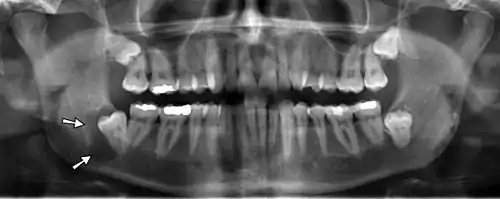

Arrows point to two vertical white lines which is how calcifications in the first part (proximal component) of the internal carotid artery appear on panoramic radiographs.

Panoramic radiographs have the capability to demonstrate a portion of the neck and display atheromas (calcifications in the carotid artery) which are an indication of both local and generalized (systemic) atherosclerosis. Atherosclerosis of the coronary arteries leading to myocardial infarction (heart attack), and atherosclerosis of the carotid artery leading to stroke are the number one and number three most common causes of death in the United States.[6]

There is interest to look at panoramic radiographs as a screening tool, however further data is needed with regards if it is able to make a meaningful difference in outcomes.[7]